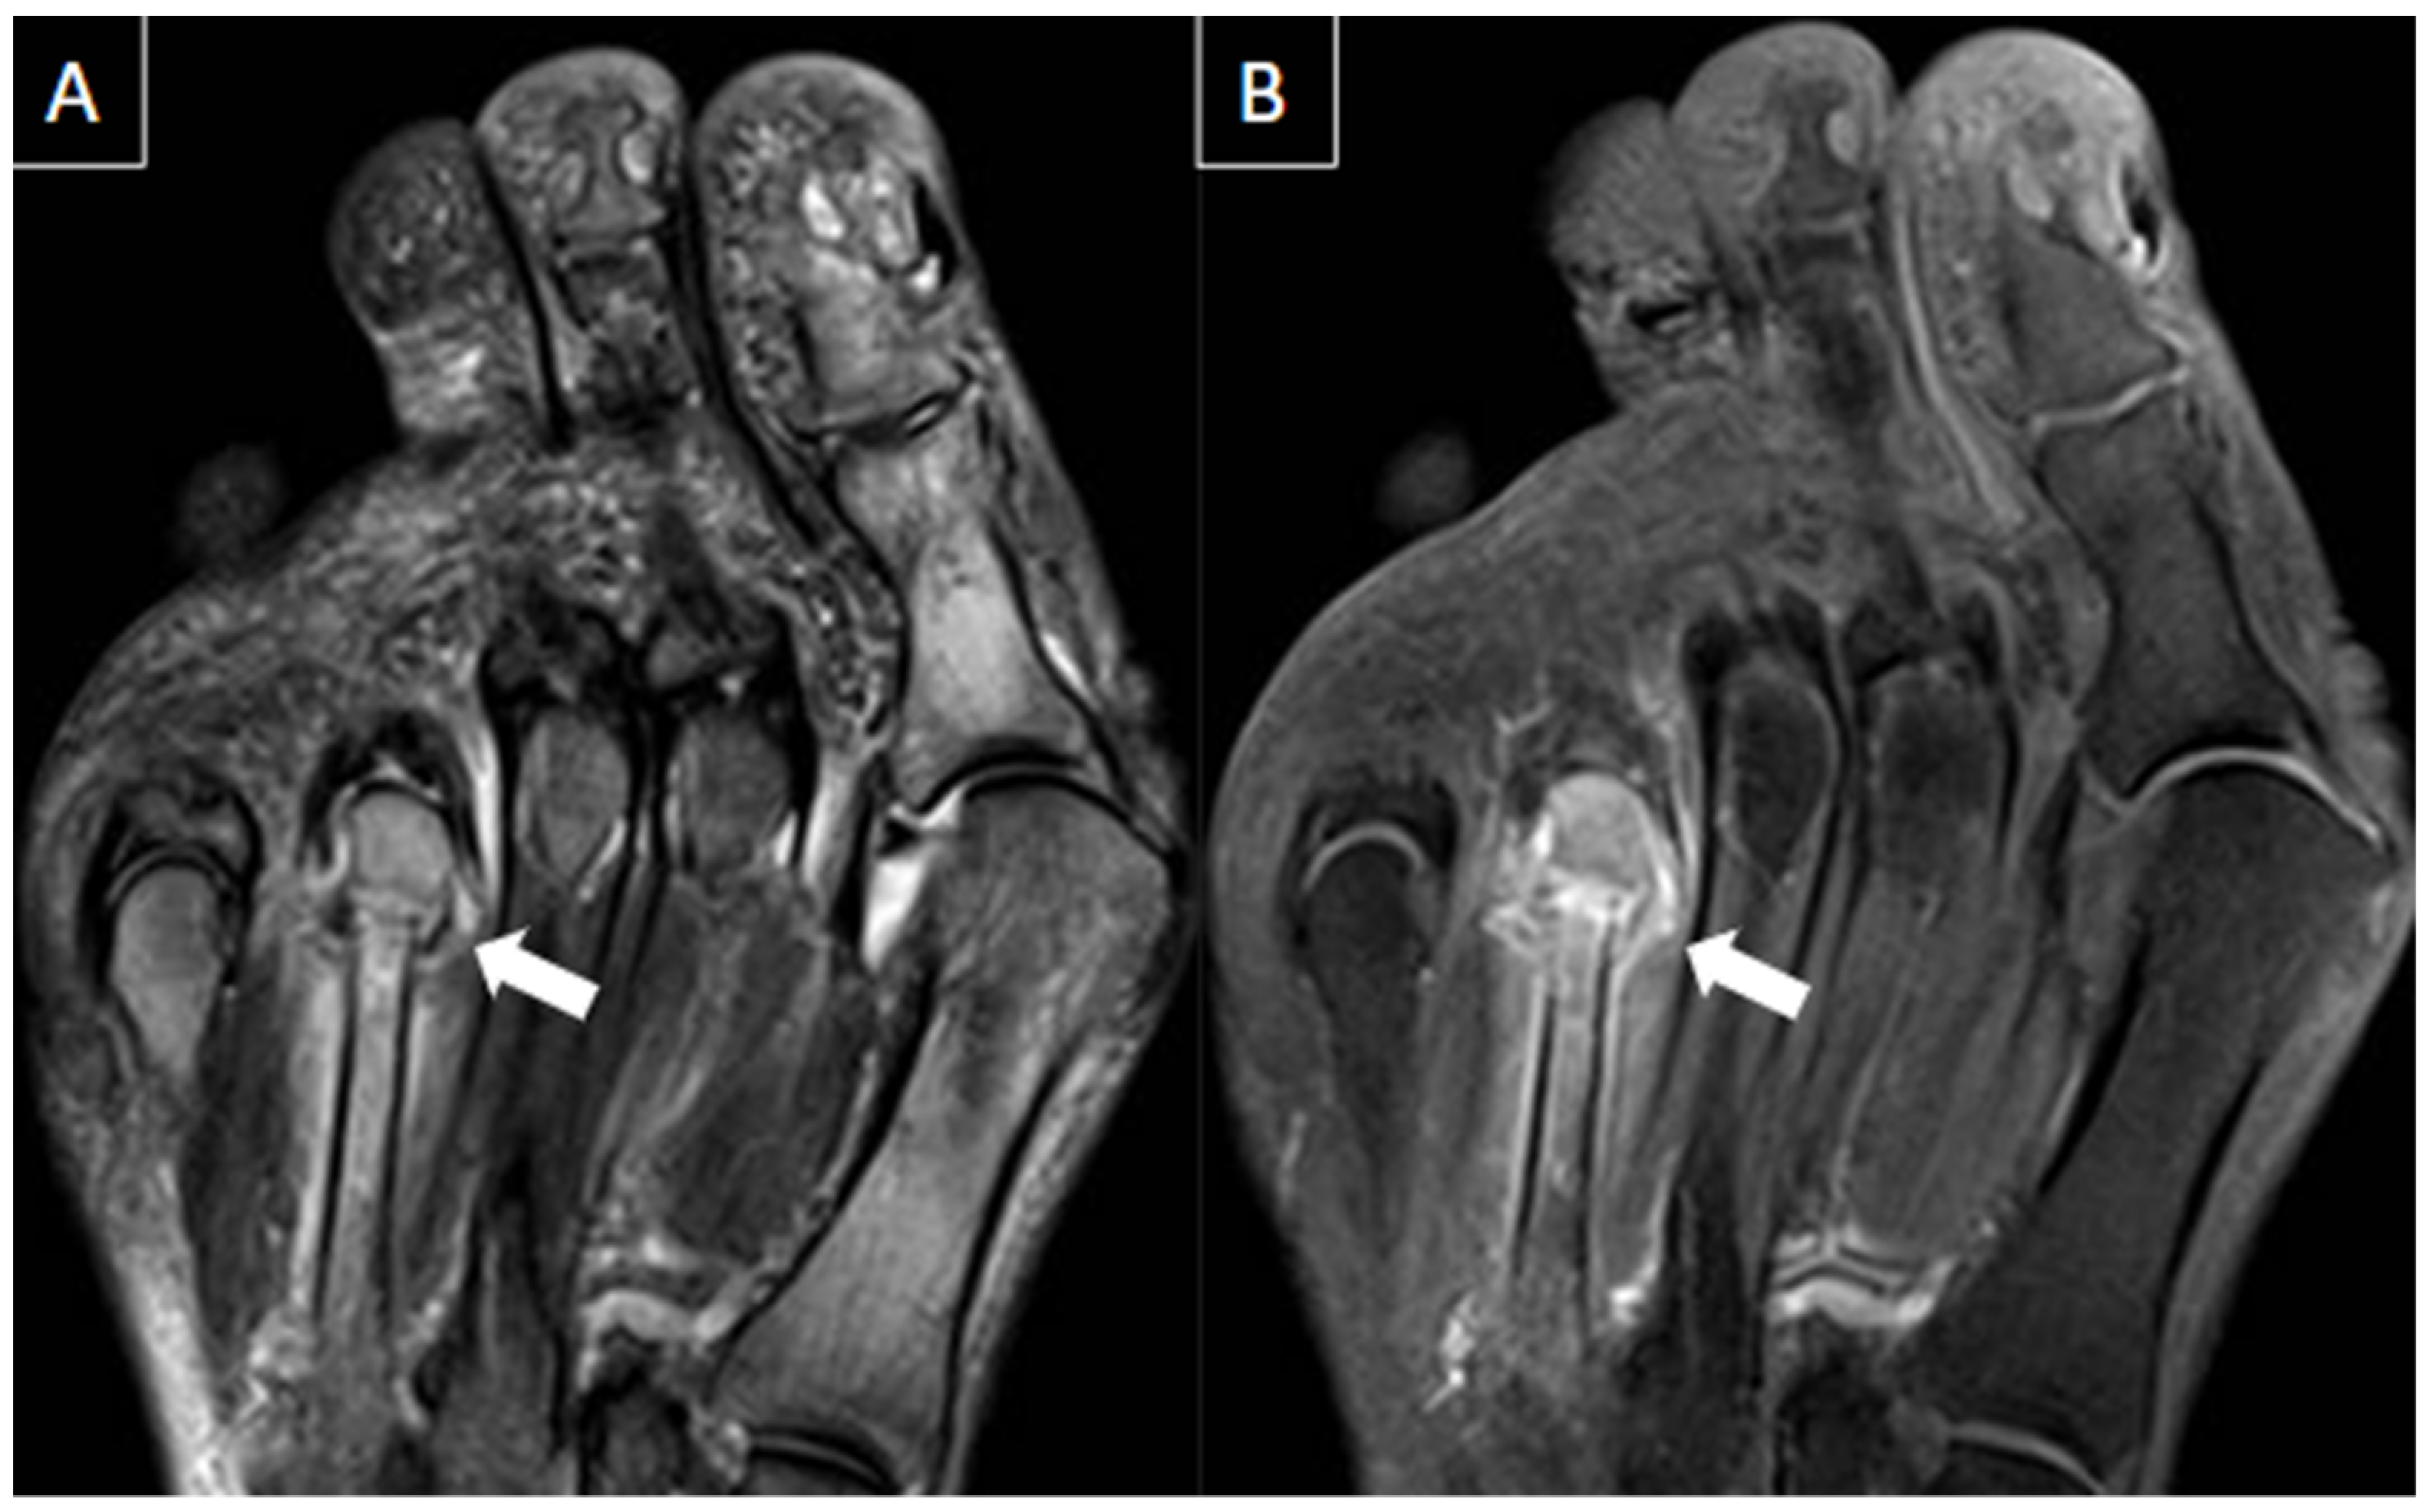

6.1. Intermetatarsal Bursitis